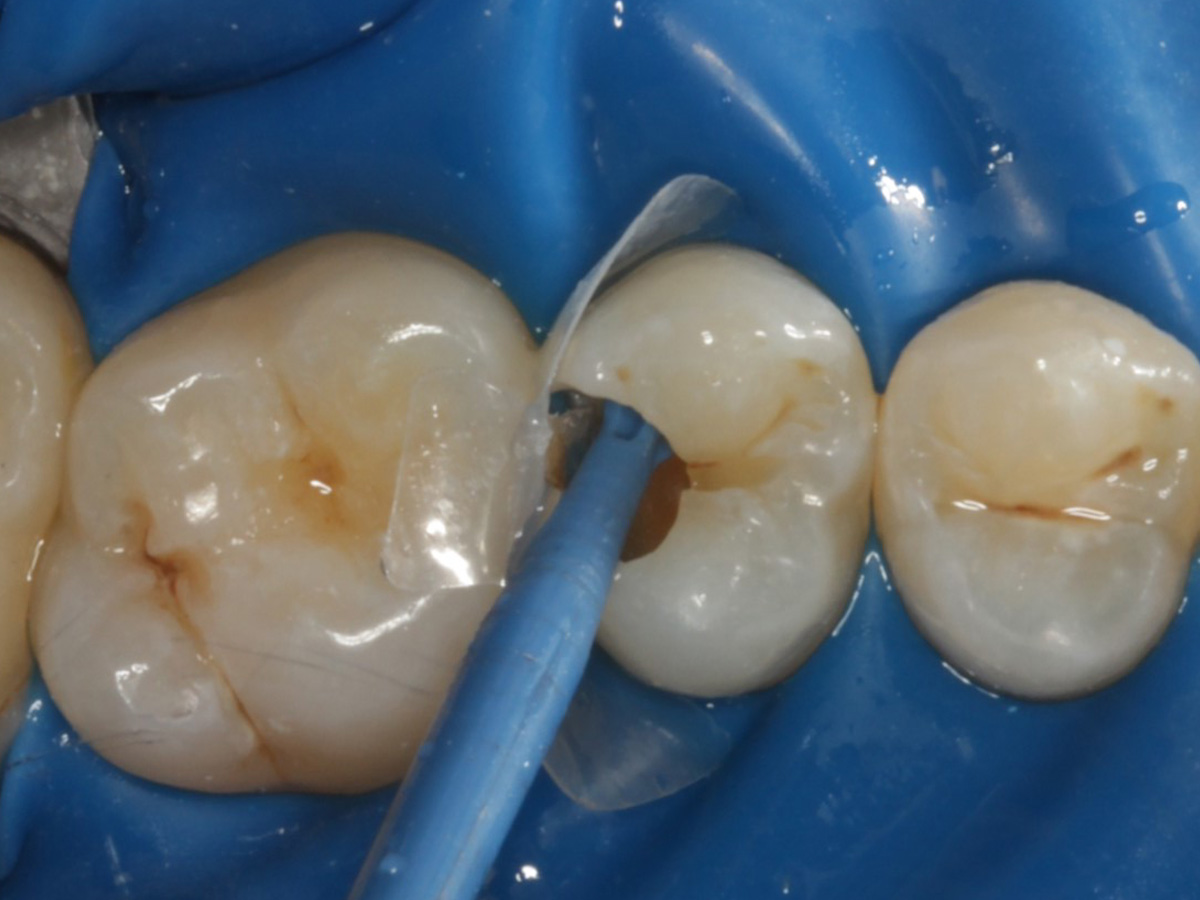

Abbildung 16

Überschussentfernung/ „Anpolieren“ u.a. trocken mit Sandpapierscheibe

Abbildung 17

Zahnseidenkontrolle: kein Überschuss, satter Kontaktpunkt